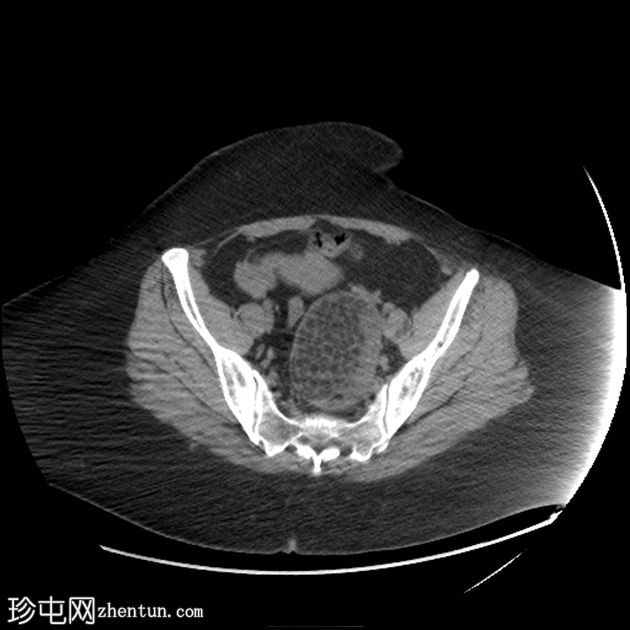

矢状位

平扫

可见一主要为囊性肿块,大小为10.1 x 7.3 x 8厘米,囊内含有脂肪球。囊壁可见钙化,并对直肠乙状结肠造成压迫。